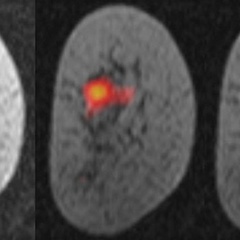

Read more at: Improved MRI scans could aid in development of arthritis treatments

Improved MRI scans could aid in development of arthritis treatments

18 June 2020

An algorithm that analyses MRI images and automatically detects small changes in knee joints over time could be used in the development of new treatments for arthritis. Thanks to the engineering expertise of our team, we now have a better way of looking at the joint James MacKay A team of engineers, radiologists and...